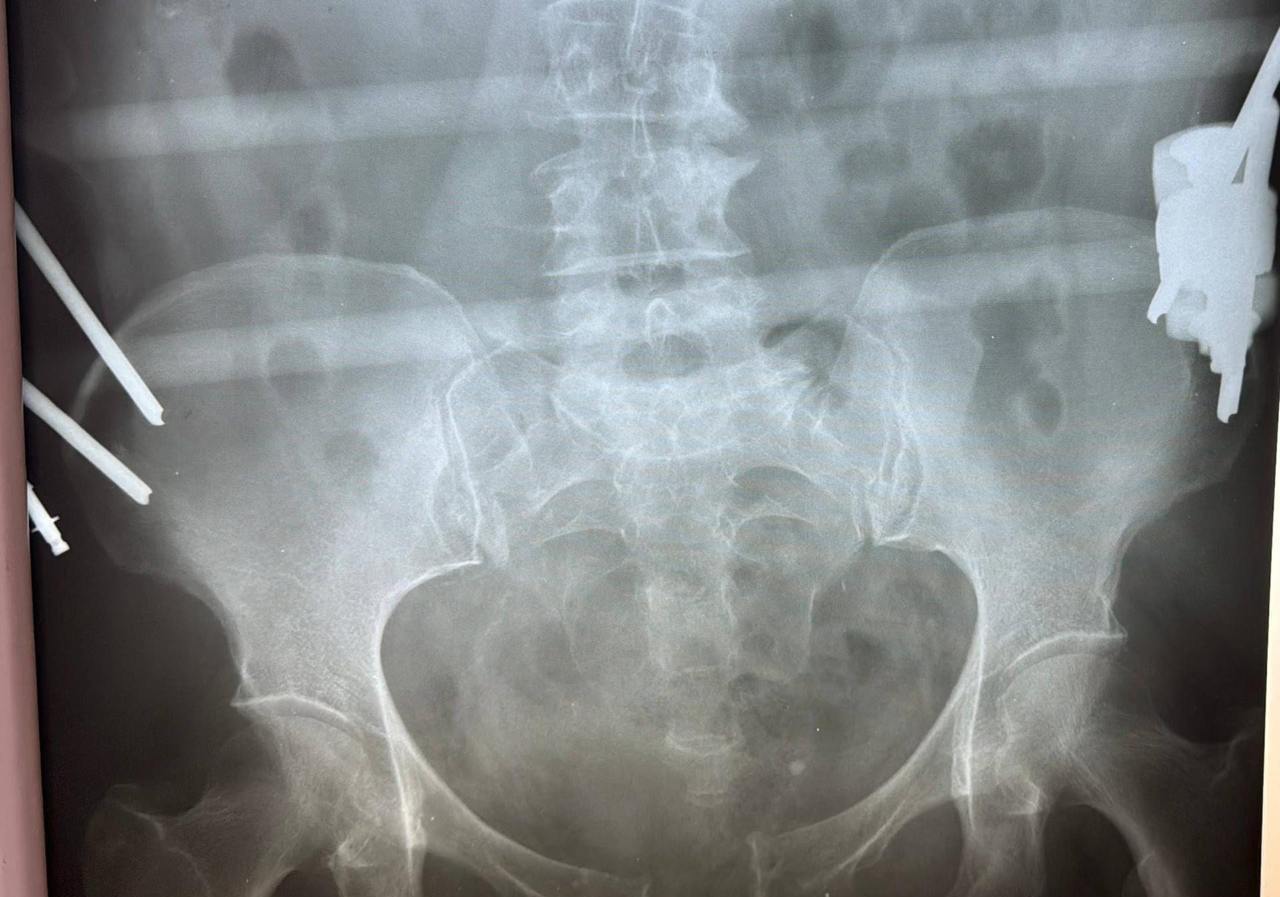

В ходе обследования врачи диагностировали сочетанную травму — разрыв лонного и крестцово-подвздошного сочленений, которые соединяют различные кости таза и играют важную роль в поддержании вертикального положения тела и распределении нагрузки. Было принято решение провести хирургическое лечение.